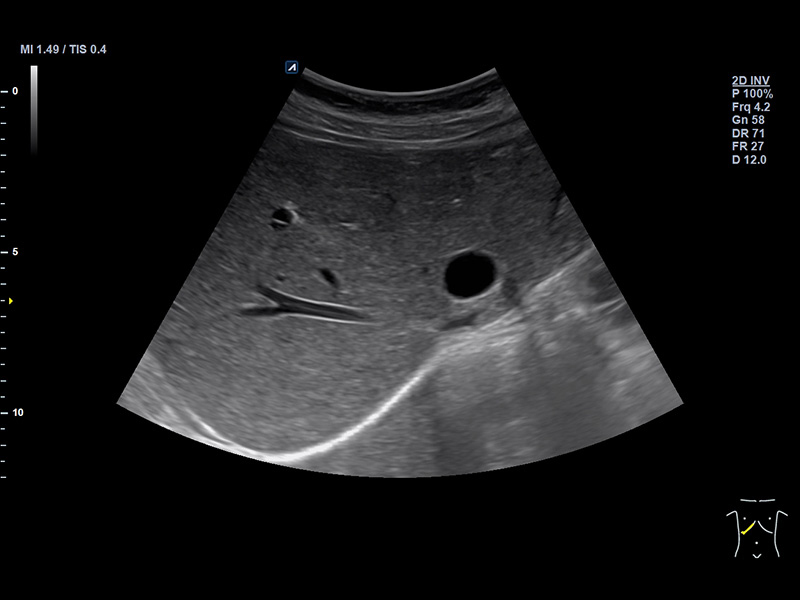

IO7-18

High frequency hockey stick (7-18MHz)

Application:

Small Parts, MSK